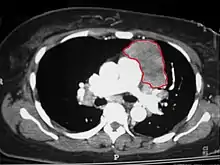

CT scan of the chest revealing a large necrotic mass in the left anterior mediastinum (indicated by the red line). Histology later established the diagnosis of a thymoma.

When a thymoma is suspected, a CT/CAT scan is generally performed to estimate the size and extent of the tumor, and the lesion is sampled with a CT-guided needle biopsy. Increased vascular enhancement on CT scans can be indicative of malignancy, as can be pleural deposits.[1] Limited biopsies are associated with a very small risk of pneumomediastinum or mediastinitis and an even-lower risk of damaging the heart or large blood vessels. Sometimes thymoma metastasize for instance to the abdomen.[5]

The diagnosis is made via histologic examination by a pathologist, after obtaining a tissue sample of the mass. Final tumor classification and staging is accomplished pathologically after formal surgical removal of the thymic tumor.